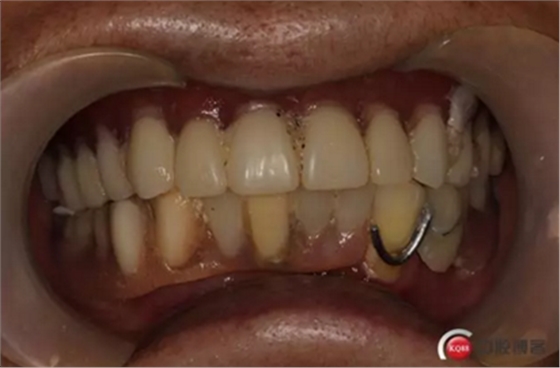

6)數(shù)字化義齒制作中心制作完成修復體臨時冠橋試戴,合適后完成最終二氧化鋯橋修復體

健康的牙齦袖口

戴牙:試戴,拍片確定邊緣密合后調整咬合,試戴一周后患者適應,咬合良好,基臺加力30N.CM,粘接劑粘固,去除多余粘結劑,拍片確定有無粘接劑殘留,并進一步微調咬合

微笑是最美的溝通語言,患者的滿意是我們的追求